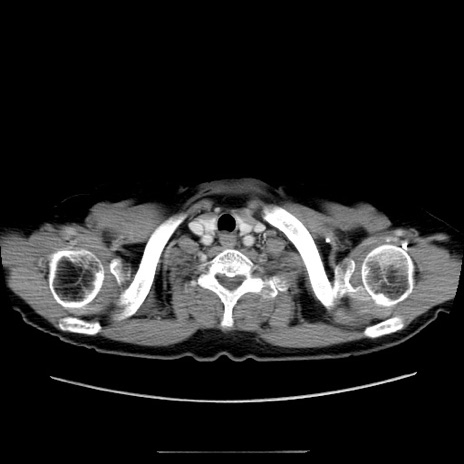

症例5(横断像)

【症例】70歳代女性

【主訴】お腹が張る

【現病歴】1週間くらい前から腹部膨満の自覚あり。昨日夜から増悪したため、本日救急外来受診。

【身体所見】意識清明、BT 36.5℃、BP 165/106mmHg、HR 80bpm、SpO2 98%、腹部:膨満、軟、自発痛・圧痛なし、触診にて不快感あり、腸蠕動音:減弱

【データ】WBC 12600、CRP 1.04